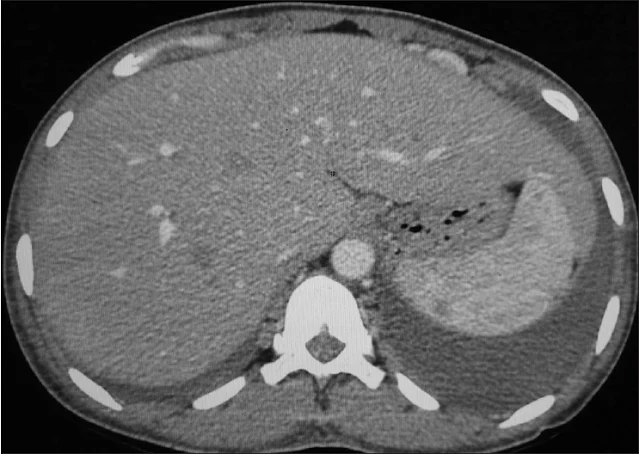

Την ηπατομεγαλία δηλαδή την αύξηση του μεγέθους του συκωτιού ποιες παθήσεις την προκαλούν;

▪ Λιπώδης διήθηση του ήπατος, στεάτωση, παχυσαρκία

▪ Διηθήσεις (Λευχαιμία, λέμφωμα, αμυλοείδωση, αιμοχρωμάτωση)

▪ Καρκίνος του ήπατος (ηπατοκυτταρικό καρκίνωμα, ηπατοβλάστωμα, ηπατικό σάρκωμα)

▪ Λευχαιμία, λέμφωμα, νευροβλάστωμα και άλλοι καρκίνοι που κάνουν μεταστάσεις στο συκώτι (καρκίνος παχέος εντέρου)